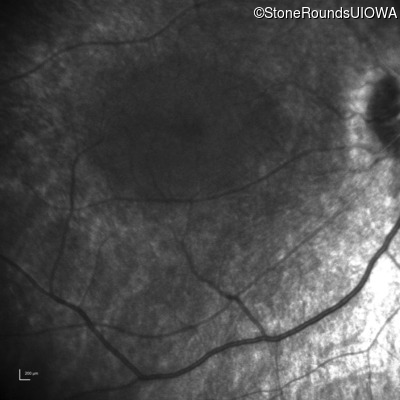

Infrared Fundus Photograph - Right - No Light Perception

Exemplar